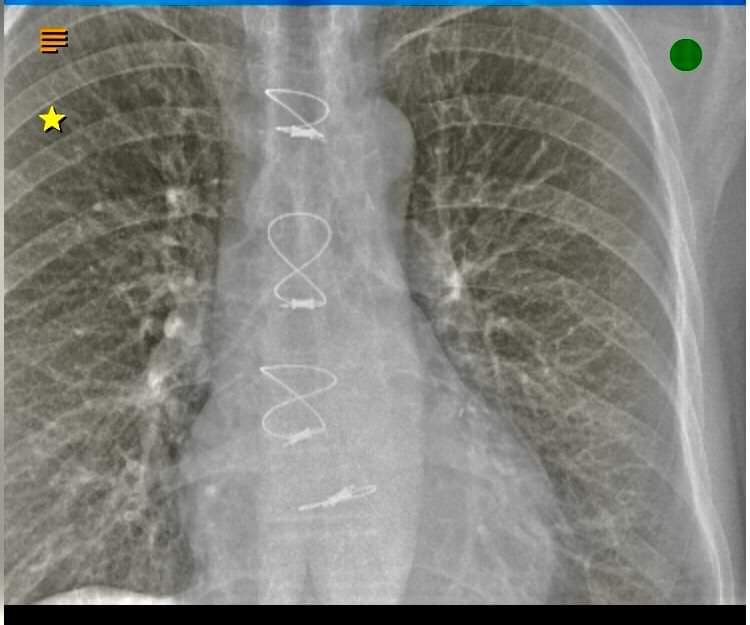

One can never have enough radiation of one’s lungs. I have had at least 10 plus chest X-rays in recent times. My chest X-rays are fascinating post surgery.